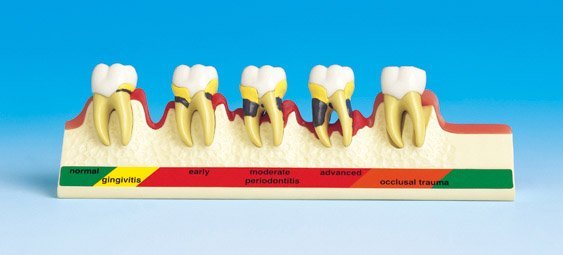

The Dental Periodontal Disease Model is a highly detailed, cross-sectional teaching tool that effectively illustrates the complete progression of gum diseaseÊ from healthy gingiva to advanced periodontitis and bone resorption. This model includes five molar teeth, each representing a specific stage in periodontal health, making it a powerful visual aid for dental professionals.

Crafted from durable resin, the model showcases healthy gums on the far left, followed by stages of gingivitis, early periodontitis, moderate periodontitis, and finally, severe periodontitis. It also features occlusal trauma, highlighting the impact of bite stress on periodontal health. This compact yet informative model is ideal for clinics, dental colleges, and chairside patient education.